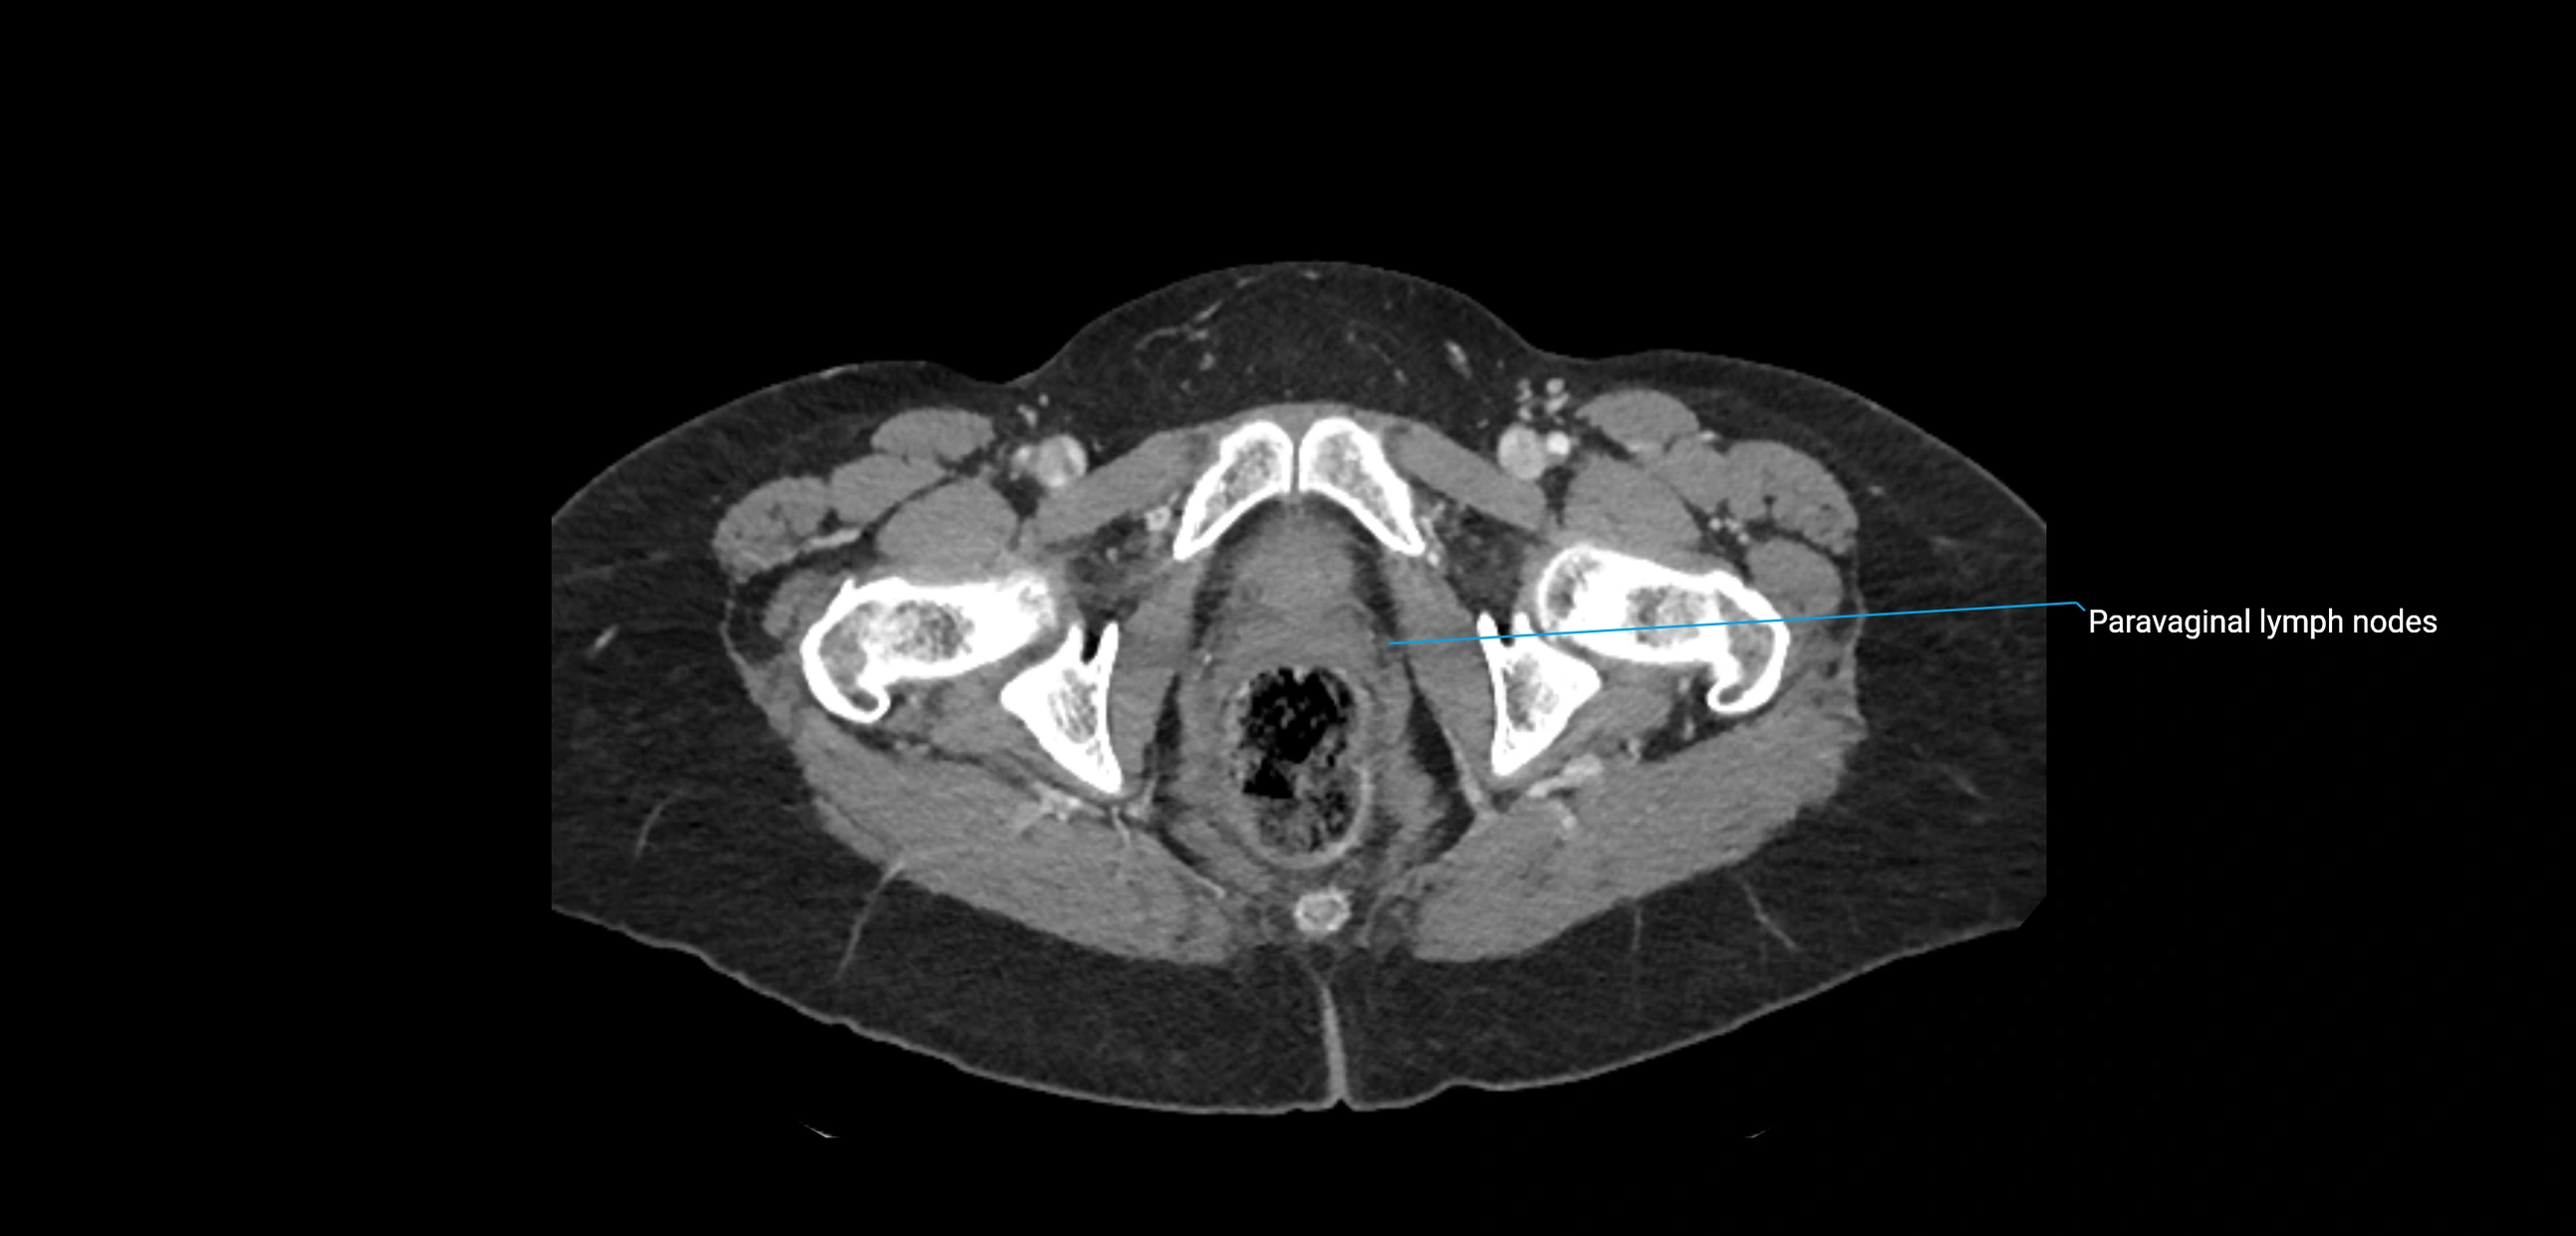

CT image

image